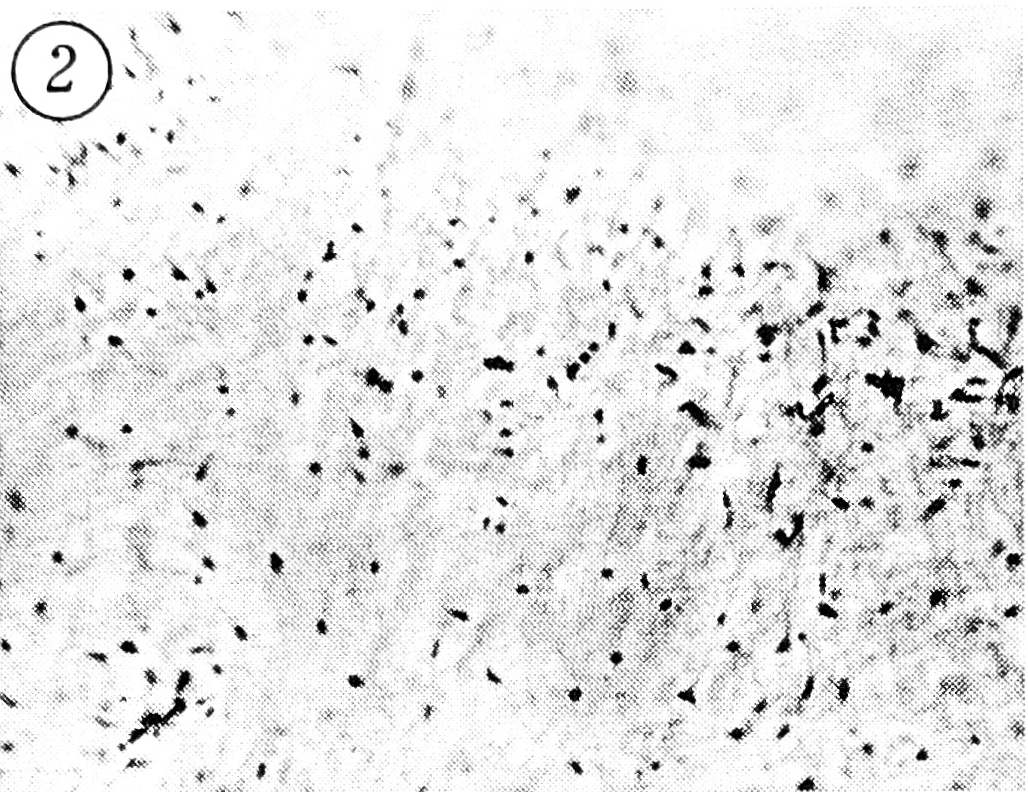

Дистрофия хрящевого интертерриториального матрикса — наиболее постоянный морфологический признак, наблюдаемый при хондролизе. Структурные изменения при этом заключаются в появлении нечетко очерченных участков потери нормальной гомогенности хрящевого матрикса, снижении его базофилии, разной степени выраженности демаскировании фибриллярности (рис. 2). В таких участках матрикс выглядит светлым, как бы прозрачным, с хорошо видимыми переплетающимися коллагеновыми волокнами, в местах наибольшего разрыхления матрикса — мелкие щелевидные полости, заполненные мелкозернистой массой. Пролиферативная реакция хондроцитов в виде гиперцеллюлярных клеточных групп наблюдается не всегда в участках выраженной дистрофии матрикса, т.е. может возникать и при минимальной степени дистрофии. В то же время участки резко выраженной дистрофии в одном и том же биоптате могут чередоваться с участками с минимальными изменениями матрикса, с резким истончением хряща и приобретением им характера волокнистого либо замещением хряща гиперцеллюлярной фиброзной тканью, иногда васкуляризованной (рис. 3).

Рис. 2. Резко выраженная дистрофия хрящевого матрикса со значительным демаскированием фибриллярности.

Окраска гематоксилином и эозином. Ув. 140.